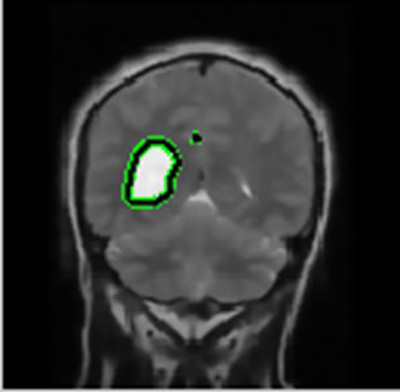

Segmentation is a way of splitting an image into constituent segments. It is generally employed to identify features and other typical information within the image. In the presented work, the segmentation leads to the identification of brain disorder that aids in the process of medical diagnosis and treatment. In the absence of tumor, the system will give the same image as output with no marking while the presence of two tumors will give 2 marks in output image and so on. The technique of split and merge segmentation is used to segment the brain image on the basis of volumetric properties that partition the image on the basis of correlation and combine similar parts to distinguish the disease.

After the preprocessing stage, the image was scanned horizontally and vertically to locate the position of cancer and image features were extracted. The pixel properties were calculated and then compared to each of its neighbors to categorize each pixel into two classes- abnormal and normal cells in MRI input image. Hidden Markov Model [12] based classifier (HMM classifier) performed classification by distinguishing pixels into true and false classes by estimating the chances of occurrence of abnormal cells in the next event depending on the properties of each pixel. The larger the size of tumor, the faster the segmentation. Split and merge segmentation was also applied to detect tumor boundary.

In this way, a boundary box differentiates the regions of image with dissimilar properties in few seconds that further lead to the exact position marking of cancer pertaining in the brain and further extracts out the cancerous portion out of the MRI image fed as an input.